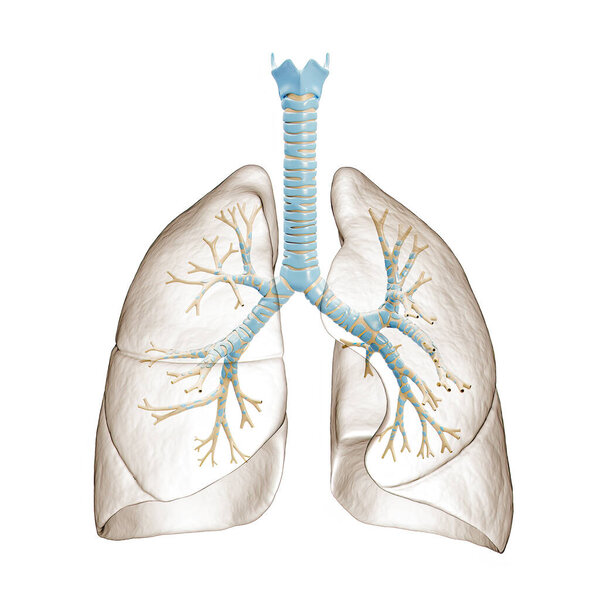

- Рак легких курильщика (с наличием депозитов смолы в бронхах).

Рак легких курильщика (с наличием депозитов смолы в бронхах).

Рак легких курильщика (с наличием депозитов смолы в бронхах).